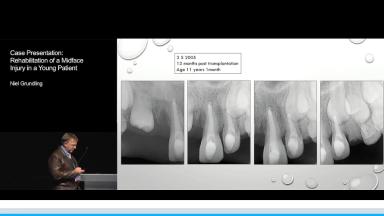

Case Presentation: Rehabilitation of a Midface Injury in a Young Patient

A 9 year old girl sustained severe soft tissue and facial bone injuries when a brick was thrown through the window of the vehicle in which she was travelling. The injuries included laceration and abrasion of the upper lip, nose and glabella, degloving of the midface, fracture of the frontal bone, nasal septum, nasal bones, nasal cartilage, dentoalveolar fracture and avulsion of teeth 12 and 11 and fracture of the incisal edges of the lower insicors.

The multidisciplinary approach to the management and rehabilitation of this young girl is presented which includes the initial, intermediate and final phases of treatment.